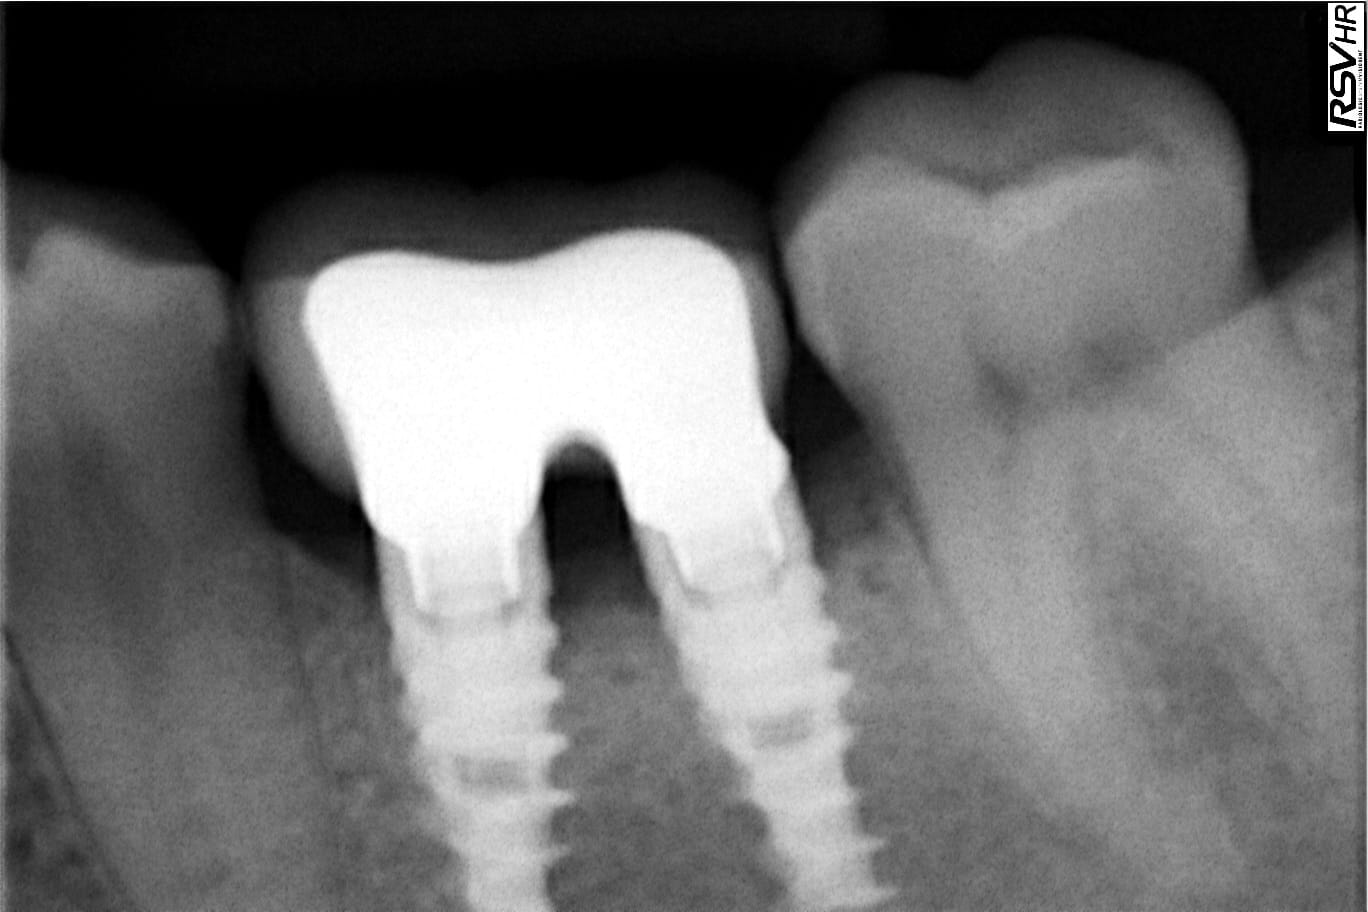

je recherche les ref de ces implants pour changer les vis ...l'une d'elle vient de casser , et le praticien a pris sa retraite ...

je pense que ça doit être un alpha bio mais pas sur !

tournevis tête hexa de 1.2 mm , longueur 8 mm

Oui, alphabio….vis en M 1.8